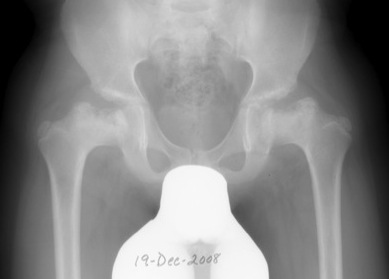

4. Remodelling

Duration : Occurs until skeletal maturity

Xray - May have flattening of the head and neck

Stuhlberg

Based on congruency & sphericity

Class 1

- normal

- 0 % OA

Class II: Spherical & Congruent

- femoral head spherical (mose circles overlaid on AP / lateral of femoral head show <2mm variation)

- At least 2 other abnormal features including Coxa Magna , Coxa Breva or Abnormally Steep Acetabulum

- 15% OA

Class III: Aspherical Congruity

- head ovoid (mushroom or umbrella shaped) and aspherical i.e Mose circles show > 2mm variation

- 60% OA in middle age

Class IV: Aspherical Congruous Incongruity

- head flat, steep acetabulum

- 75% OA usually in middle age

Class V: Aspherical Incongruous Incongruity

- head flat, normal acetabulum

- 80% OA at young age before 50